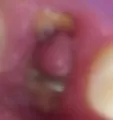

Месяц назад сломала половину переднего зуба, поначалу болел, потом беспокоить перестал. К врачу не пошла, а последние три дня он болит постоянно. Мазала лидокаином, не помогает. Начала губа верхняя под этим зубом и крыло носа болеть. И боль какая-то ноющая.

У Вас хроническое воспаление (периодонтит), и вмешательство необходимо неотлагательное.

В противном случае Вы рискуете получить отек, как следствие обострения, и возможность потерять зуб.